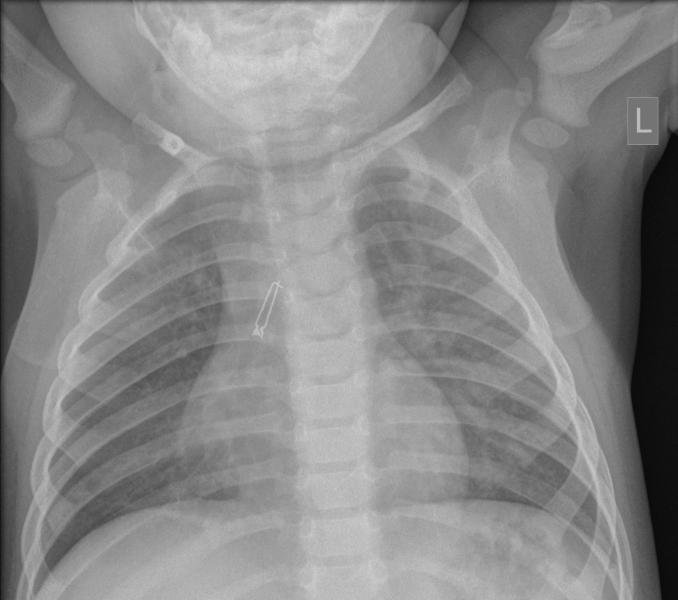

Rozpoznanie: W badaniu USG uwidoczniono koniec cewnika (biała strzałka) w żyle ramienno-głowowej lewej, a przy końcówce cewnika skrzeplinę 6x2mm, przylegającą do ściany naczynia (pomarańczowa strzałka); skrzeplina nie powoduje zaburzeń przepływu przez naczynie (ale jest przyczyną zaburzeń drożności cewnika).

Case 41b